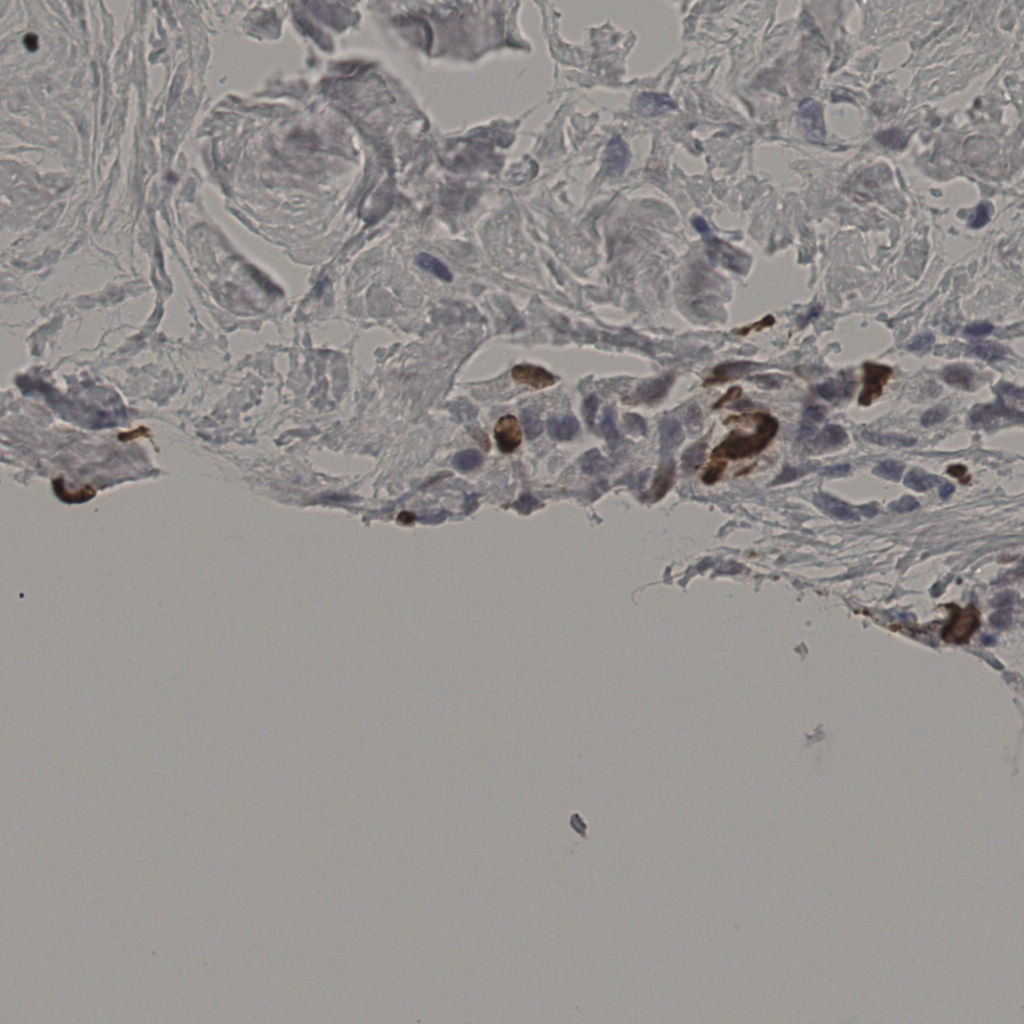

5.31%

Ki67 指数

阴 19502 阳 1093